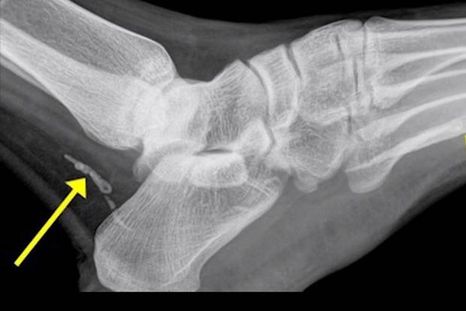

Curiosas Pensó que tenía una infección pero el diagnóstico fue impactante Los médicos fueron finalmente capaces de encontrar y curar la fuente de un crónico dolor en su pie.